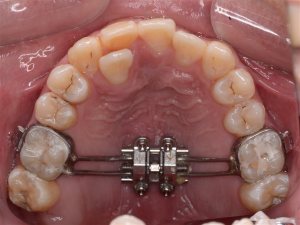

Hàm nong nhanh MSE (Maxillary Skeletal Expansion)

Trong trường hợp bệnh nhân đã bước vào giai đoạn sau của thời kỳ tăng trưởng, đường khớp giữa hàm trên bắt đầu gắn chặt hơn, các minivis có thể được cắm vào xương để hỗ trợ việc nong rộng hàm (phương pháp MARPE – Miniscrew assisted rapid palatal expander).

Phức tạp hơn, nếu bệnh nhân đã bước vào tuổi trưởng thành, đường khớp đóng hoàn toàn, mức độ bất hài hòa kích thước hàm trên lớn, phương án phối hợp phẫu thuật để mở rộng cung hàm có thể được chỉ định (SARPE – Surgical assisted rapid palatal expander).

Hàm nong nhanh có hỗ trợ của minivis (MARPE)